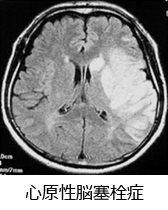

今回は抗凝固剤について考えて行きます。以前も書きましたように心房細動などの不整脈や、心機能が低下したりすると心臓内に血液がうっ滞して、心臓内(左心房)に血栓を作ることがあります。右の図のように、心臓内に血栓ができますと心臓の拍動によって左心室から脳や全身の血管に血栓が飛び、脳であれば脳梗塞、末梢の血管であれば動脈閉塞により諸症状を呈します。その血栓を防止するのが抗凝固剤の役割となります。

心房細動が原因でおこる脳梗塞は心原性脳梗塞と呼ばれ、脳梗塞の中でも大変予後が悪いことで知られています。亡くなられた小渕首相や、右片麻痺・失語症が残存している長嶋茂雄巨人軍終身名誉監督もこのタイプの脳梗塞をおこされています。